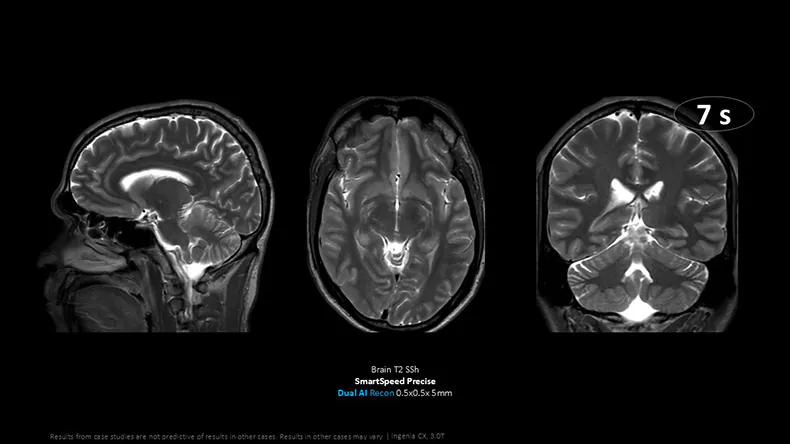

Continuing its momentum in AI-powered MR, Philips has received FDA 510(k) clearance for SmartSpeed Precise [1] MR’s latest deep learning reconstruction software, marking a major milestone in the journey toward autonomous, personalized MRI. SmartSpeed Precise is the industry’s first integrated dual AI solution, delivering up to 3x faster scanning [2] and up to 80% sharper images [3]—all in just one click.

SmartSpeed Precise delivers a powerful combination of speed, precision, and simplicity that directly addresses the most urgent challenges facing radiology departments today. With scan times up to three times faster [2], providers can reduce patient backlogs by increasing throughput without compromising quality, reducing diagnostic scan times to levels not seen before, including a less than 10-second brain scan. The system delivers up to 80% sharper images [3], boosting diagnostic confidence in complex areas like neurology, oncology, and cardiology. Its streamlined, one-click workflow promotes consistent imaging across teams and patient anatomies, with easy protocol optimization ensuring reliable results, even in challenging cases like pediatric, elderly or uncooperative patients.